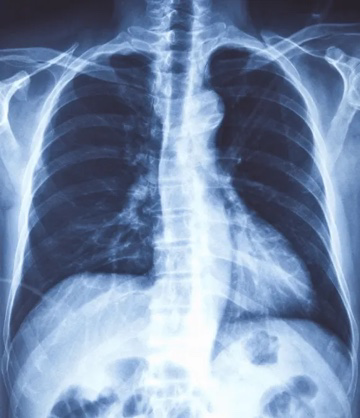

成像的原理基于X线本身的特性和人体组织结构的特点。X线具有很强的穿透性,能穿透人体的组织结构,而人体组织之间存在着密度和厚度的差异。所以X线在穿透过程中被吸收的量不同、剩余的射线又利用其荧光效应和感光效应在荧屏或X光片上形成明暗或黑白对比不同的影像。

图源:网络

肺部疾病,可以判断患者肺部是否有炎症、肺结核、肺肿瘤、肺脓肿、胸腔积液、气胸、支气管扩张、胸膜增厚等;

判断是否有纵隔增大,或纵隔占位性疾病;

判断患者输尿管结石的位置,或节育环的位置;

判断患者是否有骨骼系统疾病,比如骨折、骨肿瘤等;

用于检查胃肠道系统疾病,比如可以做X光下的钡餐透视。

优点:快捷、价格便宜。

缺点:在X光检查中骨骼的呈像相对清晰,一般多用于粗看骨折或骨质增生等骨骼健康情况。但X光检查只能提供二维的平面影像,成像也容易受衣物、首饰甚至过厚的软组织影响,所以一般作为初步检查使用。